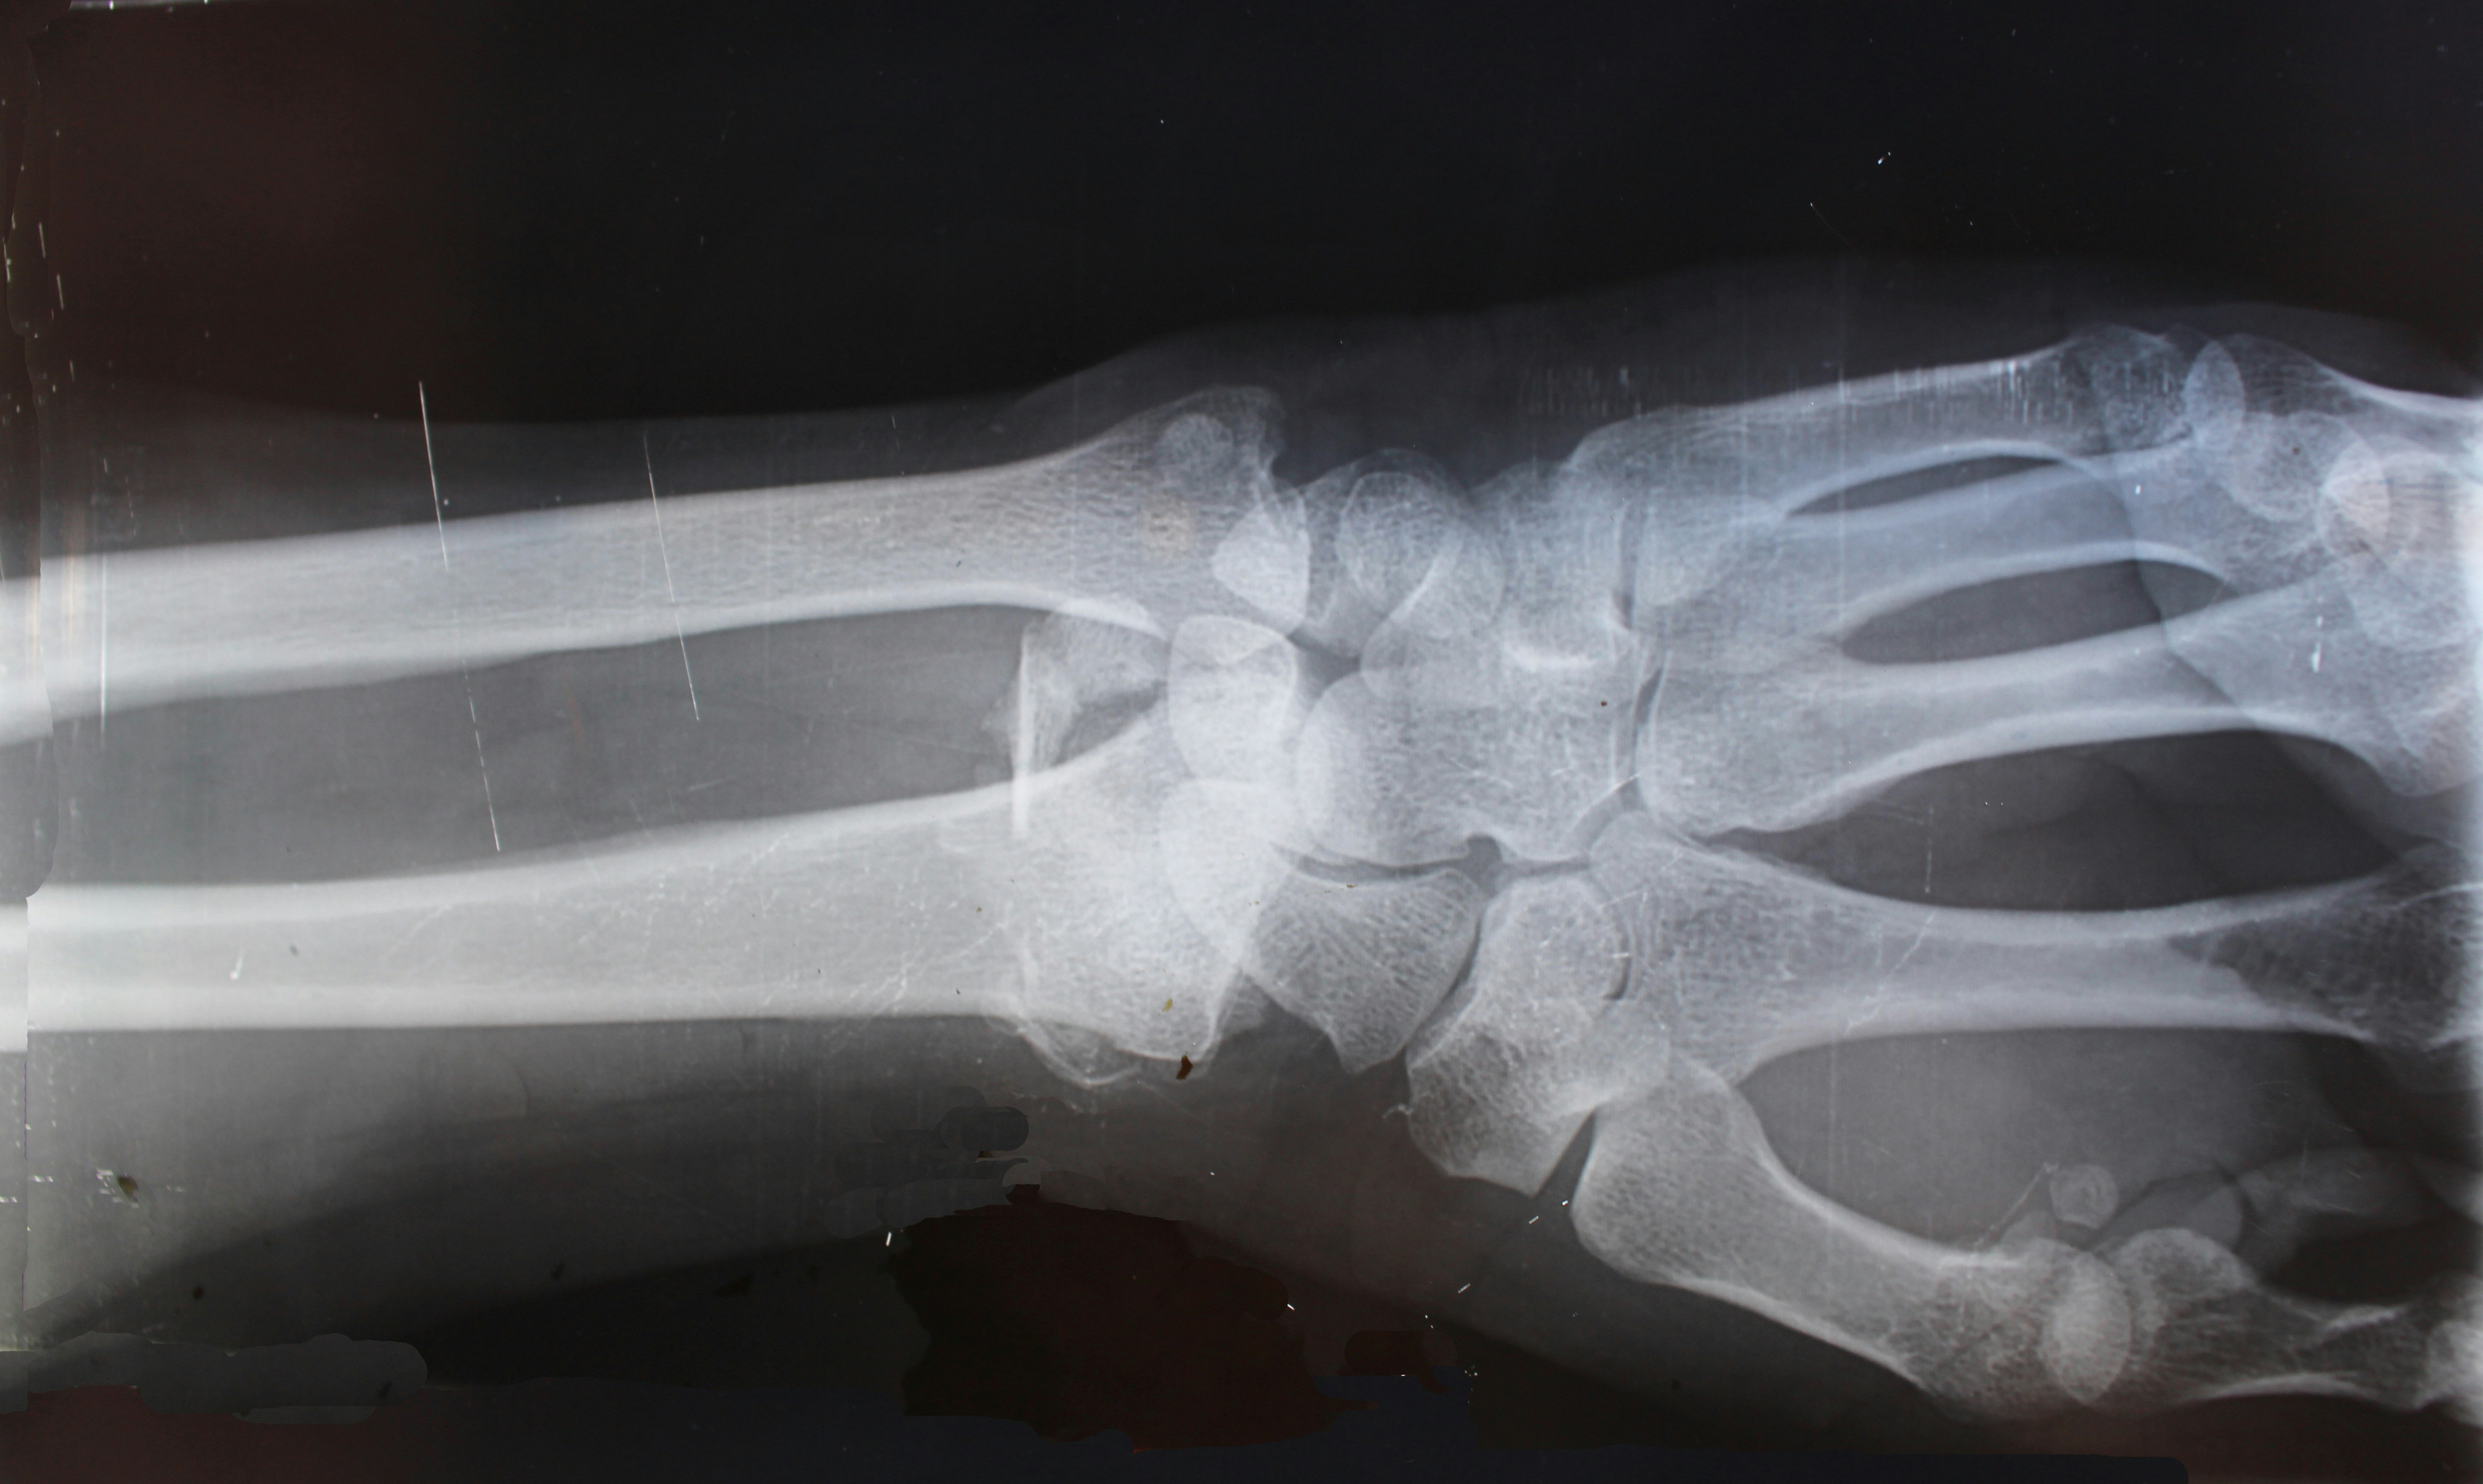

The Essential Role of X-Rays in Ensuring Safe and Effective Chiropractic Care

Chiropractic care plays a vital role in promoting good health, alleviating pain, and addressing muscle and bone issues. X-ray imaging is necessary for your Chiropractic doctor to better understand the spine and musculoskeletal structures, prevent harmful adjustments and to optimize treatment results.